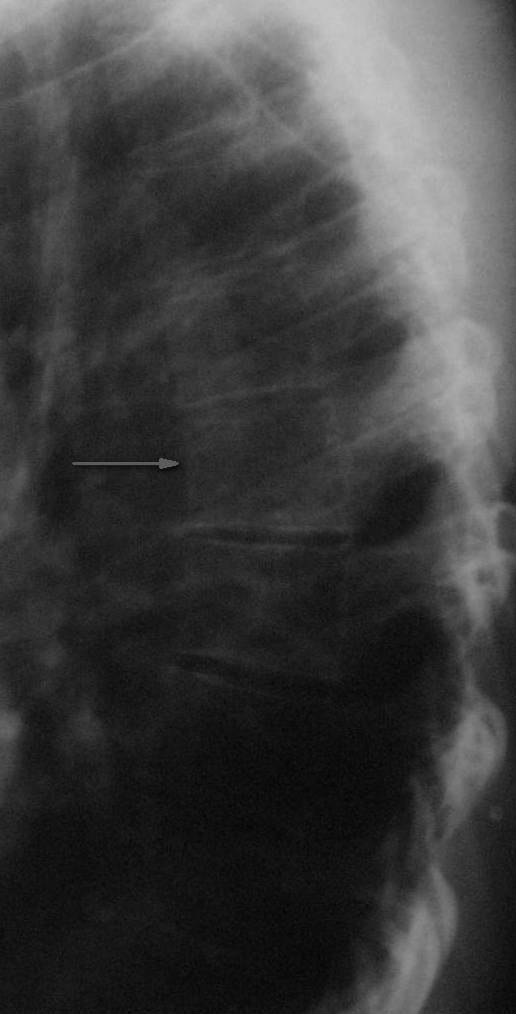

Конечно же можно. Седьмой грудной позвонок указан стрелкой.

По боковой рентгенографии видно клиновидную деформацию не только Т7, но и Т8. Клиновидная форма тела Т7 скорее всего обусловлена саондилодисплазией такой же как и у тела Т8. По нижнему краю тела Т7 четко просматривается склероз замыкательной пластинки, высота диска Т7-Т8 явно снижена по сравнению с Т8-Т9.

Я думаю, рентген картина соответствует перенесенной спондилодисплазии и развивающемуся остеохондрозу на данном уровне и не связанна с травмой.

Спасибо за мнение. Один из вопросов, казалось бы, решен - изменения тел позвонков не травматической этиологии. Остается один вопрос - как идентифицировать изменения (дефекты) замыкательных пластинок, на КТ описанные как переломы;кстати врачи КТ категорически не согласились с мнением Юрия Алексеевича, что это венозный рисунок.

Довольно часто, развитие Шиермана-Мау сопровождается формированием грыж Шморля. Условием для образования данного вида протрузии служит изменённая замыкательная пластинка, нарушение её целостности и как следствие формирование грыжи. Возможно, в Вашем случае мы как раз и наблюдаем развитие данного процесса в виде нарушения целостности замыкательной пластинки.